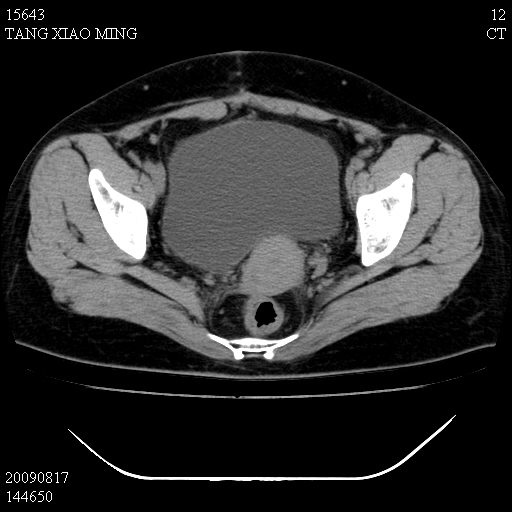

标题: CT21692:盆腔病变

女,33岁,右下腹痛2年余,既往宫外孕病史,如在我院手术,结果下周公布,

可能的诊断。1子宫内膜异位【子宫腺肌症并右卵巢巧克力囊肿】;2 右卵巢囊腺瘤。子宫肌瘤

1)考虑卵巢巧克力囊肿,不排除卵巢囊腺瘤。2)子宫肌瘤可能。

卵巢囊腺瘤,子宫肌瘤,直肠壁厚,不除外占位.